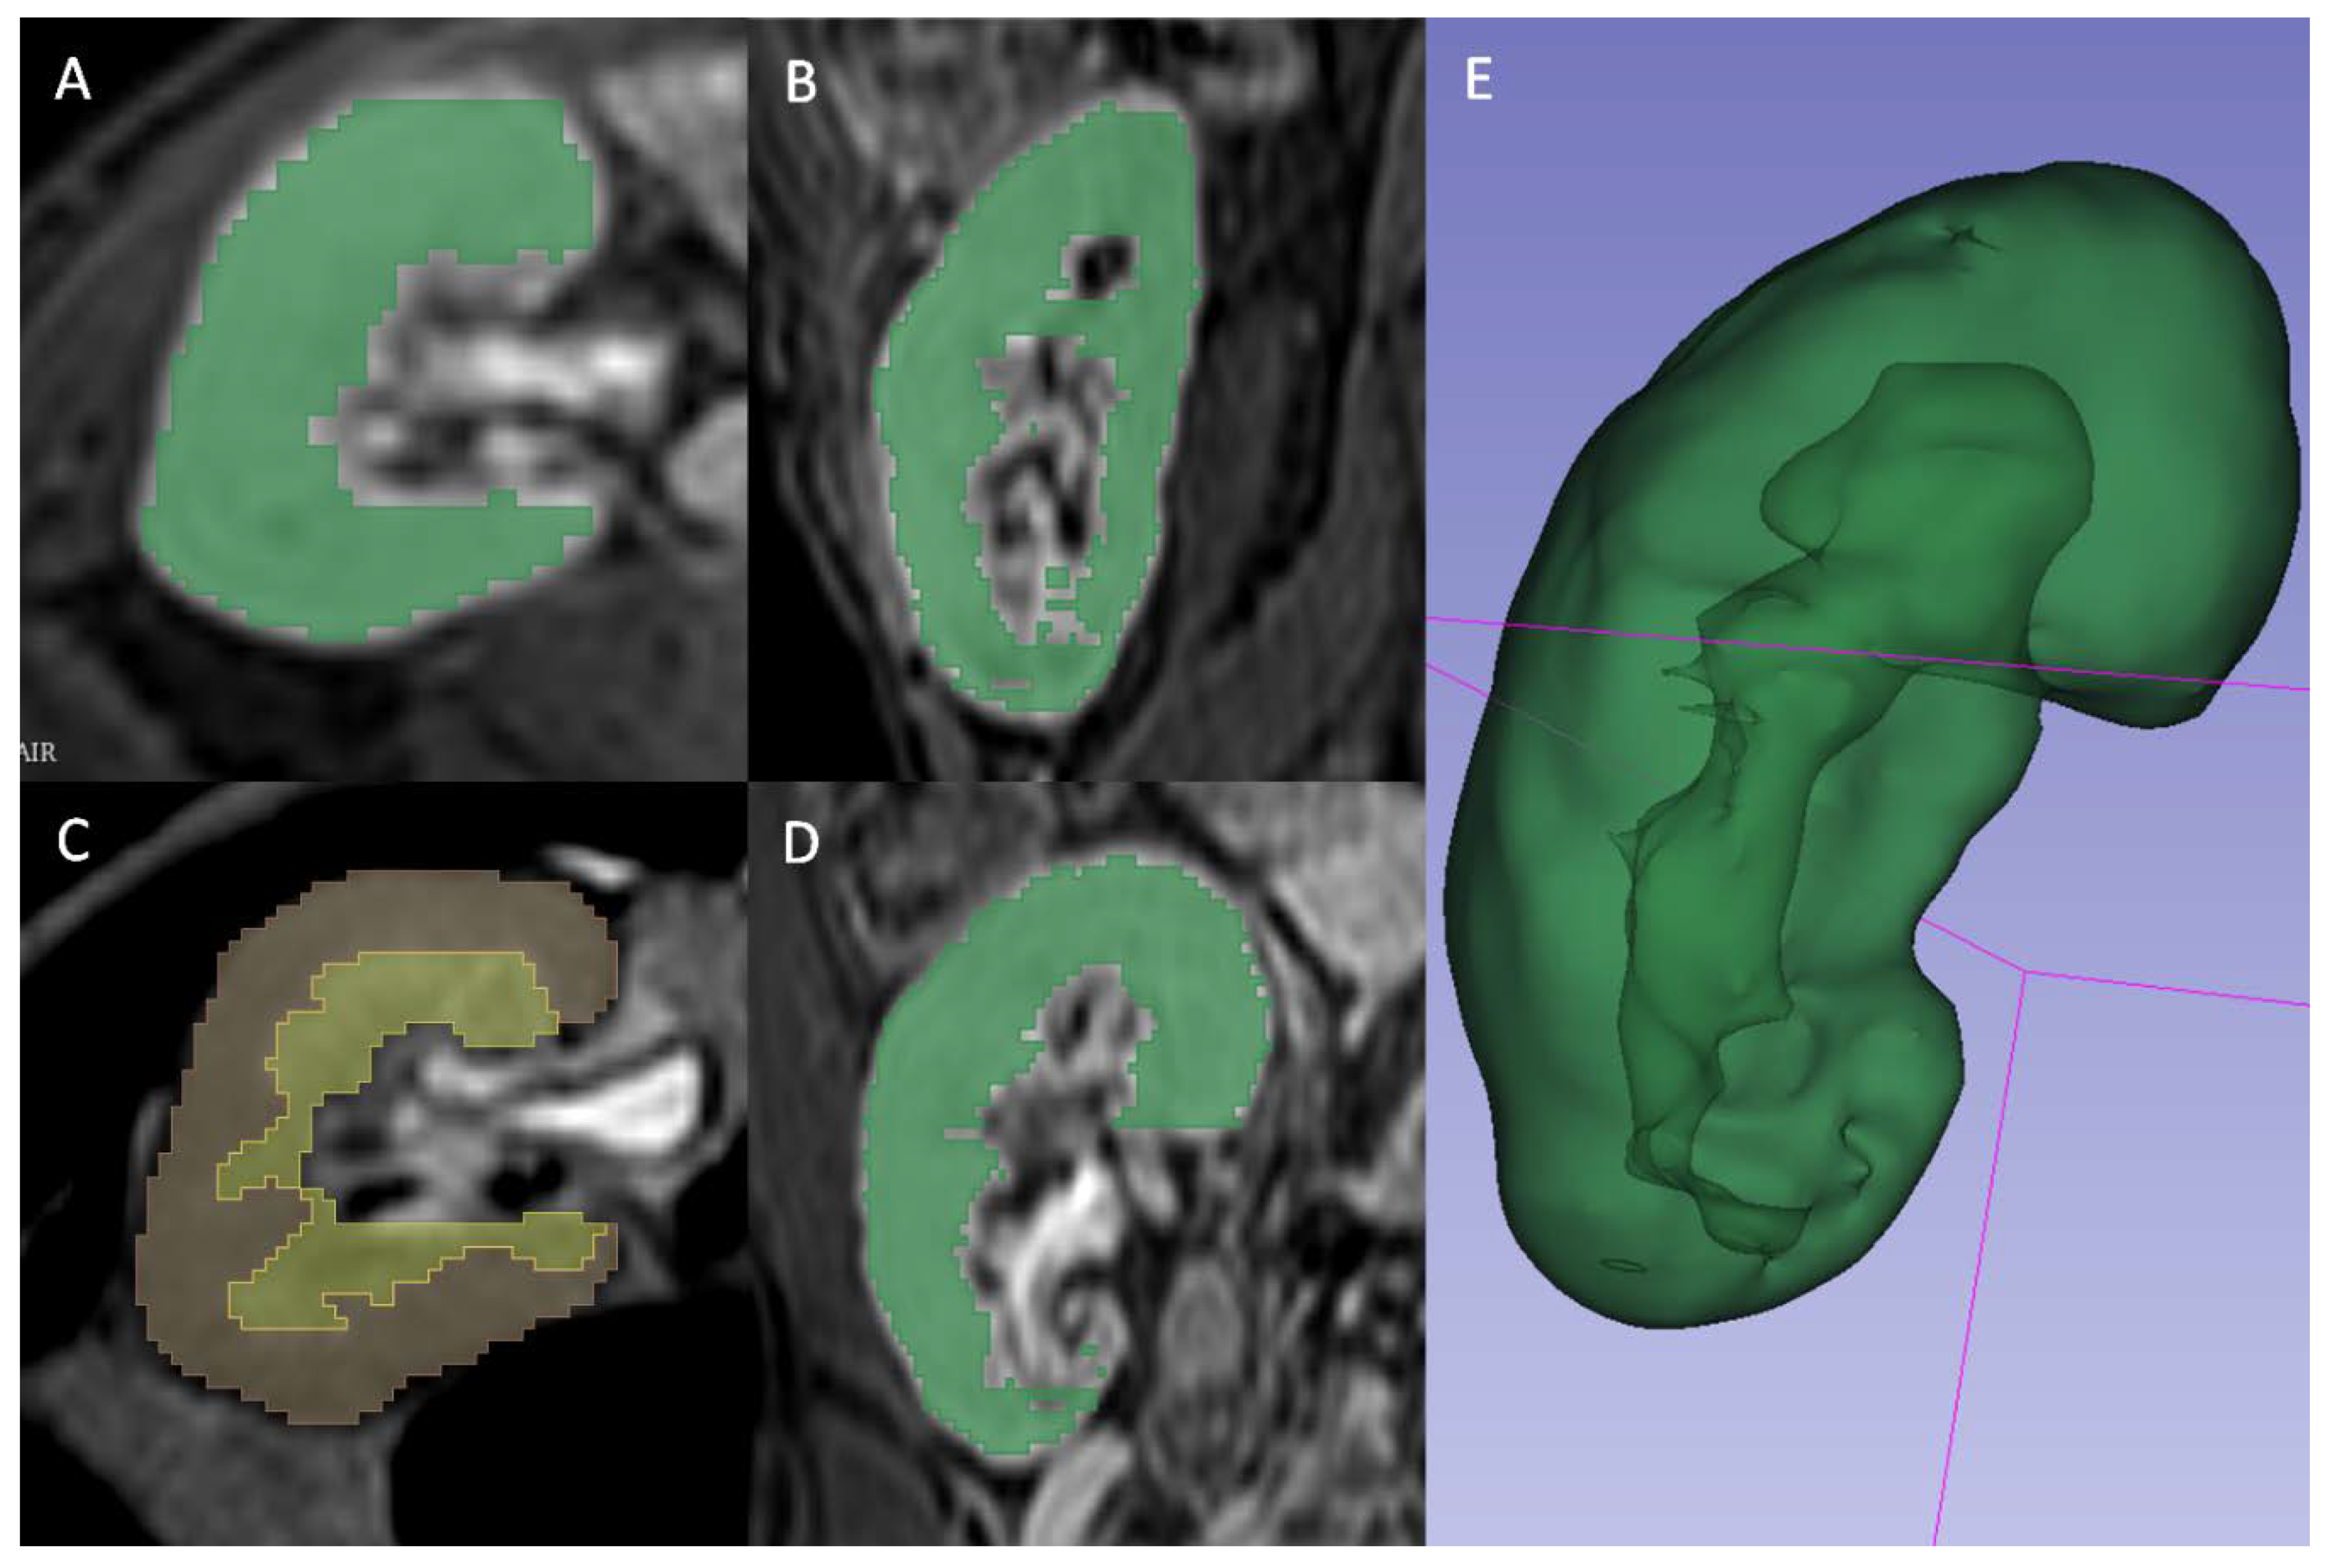

A radiologist (FM) blinded to the clinical outcomes segmented the transplanted kidneys using 3D Slicer software version 4.10.1 [17]. For T2 2D images the manual contouring tool was used to select the whole parenchyma (Fig. 2A), the medulla (Fig. 2B) and the cortex (Fig. 2C) obtained through previous segment subtraction. For T1 3D postcontrast images, the semiautomatic contouring tool based on intensity levels was used for the delineation of the whole parenchyma only, since it was not possible to reliably differentiate cortex and medulla (Fig. 2D). A different tool was adopted because on T2 weighted sequences, the intensities of parenchyma and surrounding tissue were too similar to be reliably differentiated by the semiautomatic contouring tool. Moreover, the higher number of images of T1 3D sequences, caused by a lower thickness, made the manual contouring tool too slow to be adopted.

Figure 2. A, B and D: Gradient Echo T1 weighted 3D venous phase post contrast sequence segmented in whole parenchyma only through the intensity-levels based semiautomatic contouring tool and depicted in axial view (A), sagittal view (B) and coronal view (D). C: Single Shot T2 weighted sequences segmented with 3D slicer manual contouring tool respectively subdivided in medulla (yellow) and cortex (red). E: 3D rendering of whole parenchyma using T1 3D segmentation.